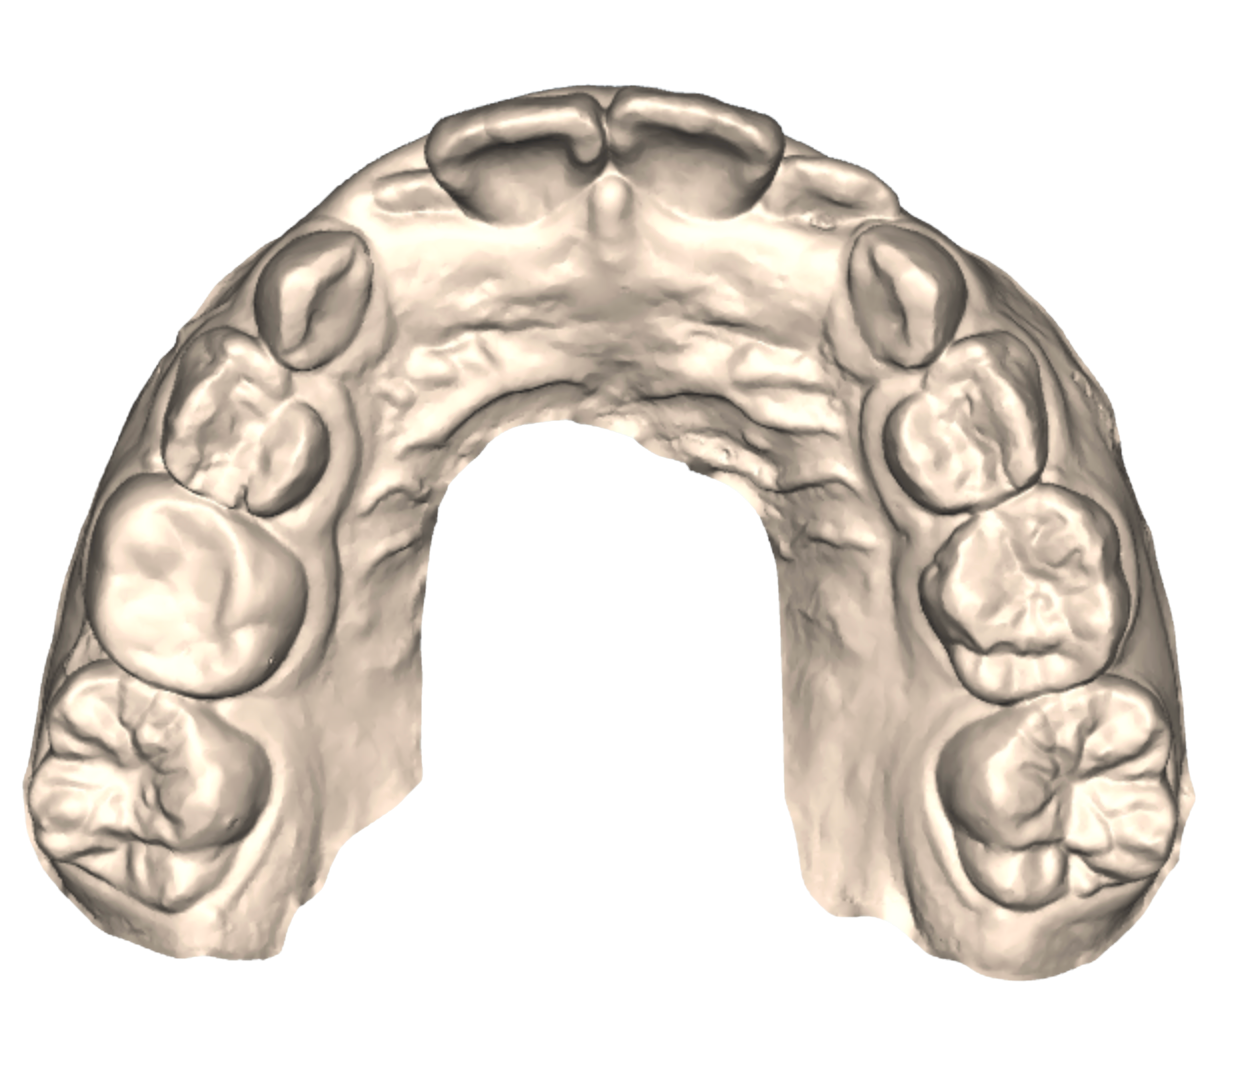

Why Age 7–10 Is a Critical Window

During this time, the jaws are still developing. This gives us as orthodontists a unique opportunity to ensure healthy development in ways that are nearly impossible to achieve later in life.

Jaw Development

Narrow Jaw

Before

Expanded Jaw

After

Dr. Gerald Kim approaches early orthodontic care with custom appliances made differently for each case. Dr. Kim helps parents understand what’s happening beneath the surface. His philosophy is conservative and intentional: intervene when necessary, monitor when appropriate, and always prioritize your child’s long-term health.